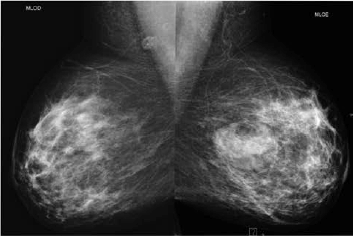

Paciente de 40 anos realizou esta mamografia para rastreio, sendo assintomática. A ultrassonografia realizada em outro serviço, 6 meses antes da mamografia, demonstrou pequeno nódulo hipoecoico de 1,5 cm no QSE da mama direita e nenhuma lesão na mama esquerda. Assinale a alternativa correspondente à hipótese diagnóstica da imagem nodular da mama esquerda observada na mamografia.